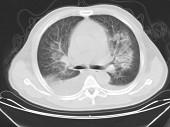

男,32岁,CT图像如图,最可能的诊断为 ( )A.肺水肿并双侧胸腔积液B.周围型肺癌C.肺动静脉瘘D.肺错构瘤E.炎性假瘤

问题 男,32岁,CT图像如图,最可能的诊断为 ( )

选项 A.肺水肿并双侧胸腔积液 B.周围型肺癌 C.肺动静脉瘘 D.肺错构瘤 E.炎性假瘤

答案 A